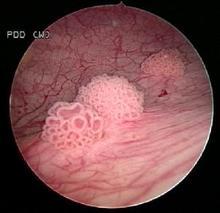

膀胱肿瘤的镜下表现